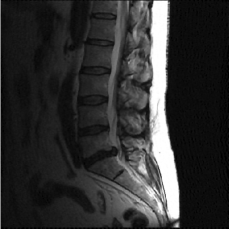

(c) Lumbar spine

Refer to caption

Figure 2: Test Images.

We turn now to test TDIHT for high dimensional signals. We test the performance of several MRI images: the Shepp-Logan phantom, FLAIT brain image, T2 Sagittal view of the lumbar spine and the circle of Willis. The first image is of size 256×256256256256\times 256, while the other are of size 512×512512512512\times 512. They are all presented in Fig. 2.

We focus on the recovery of these images from a few number of Fourier measurements. With 𝛀𝛀{\mathbf{\Omega}} set to be the undecimated Haar transform with one level of resolution (redundancy four) and 𝐃𝐃\mathbf{D} its inverse transform, we succeed to recover the phantom image using only 181818 sampled radial lines, which is only 6.5%percent6.56.5\% of the measurements. This number is only slightly larger than the number needed for GAP, relaxed ASP (RASP) and Relaxed ACoSaMP (RACoSaMP) in [10, 38]. The advantage of TDIHT over these methods is its low complexity as it requires applying only 𝐌𝐌{\mathbf{M}} and its conjugate and 𝛀𝛀{\mathbf{\Omega}} and its inverse transform while in the other algorithms a high dimensional least squares minimization problem should be solved. Note also that for AIHT and RAHTP the number of radial lines needed for recovery is 353535 and for IHT (with the decimated Haar operator with one level of resolution) we need more than 505050 radial lines.